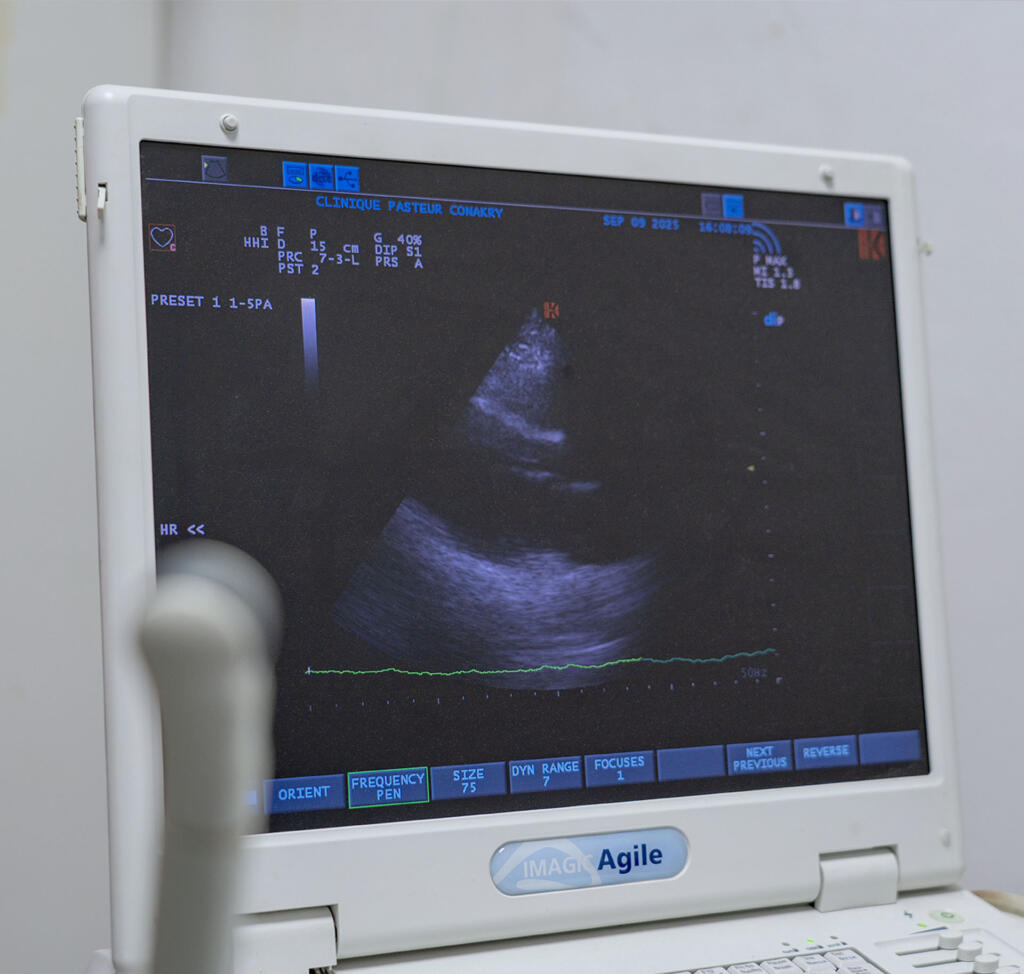

Échographie à la Clinique Pasteur Guinée Conakry

Le service d’échographie de la Clinique Pasteur Guinée Conakry met à disposition des patients une technologie moderne et précise pour le diagnostic médical. L’échographie est un examen d’imagerie non invasif, indolore et sans danger, qui utilise les ultrasons pour visualiser les organes internes et détecter d’éventuelles anomalies.

- échographie cardiaque et vasculaire,

Chaque examen est réalisé avec soin et interprété immédiatement par nos médecins afin de garantir un diagnostic fiable et rapide.